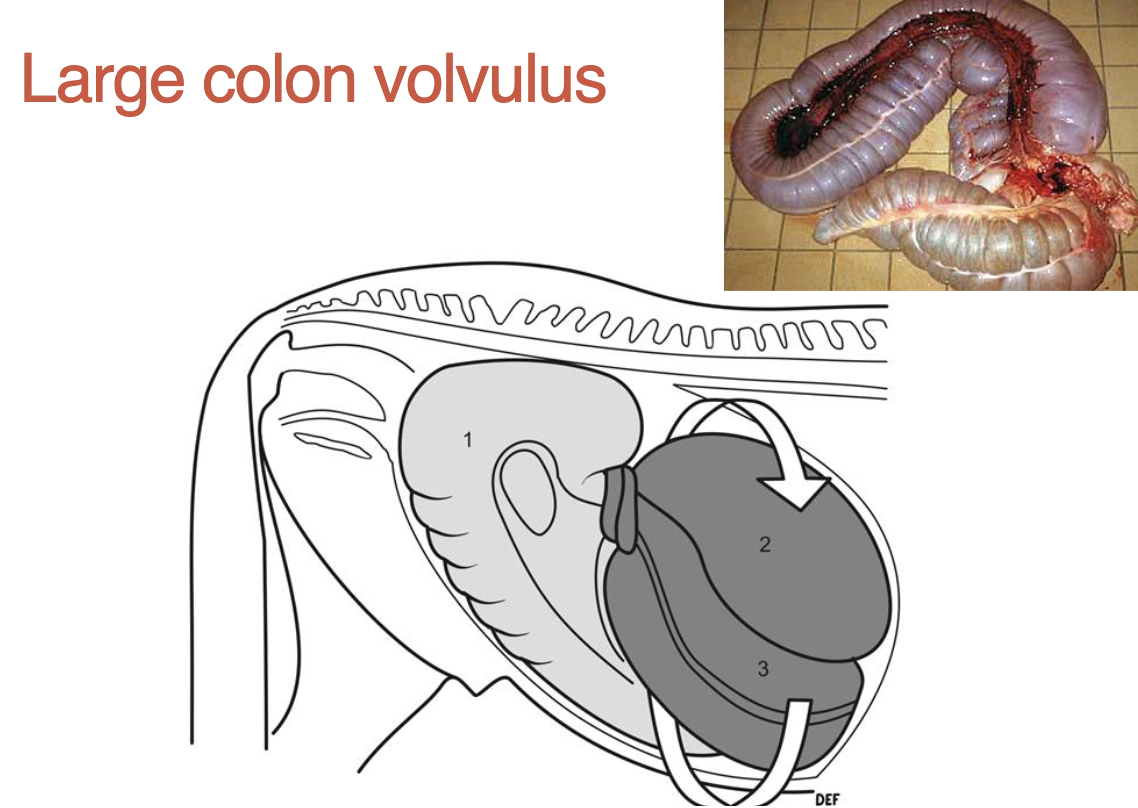

what is a large colon volvulus

twist on mesentery (location of blood vessels, cuts off supply & colon dies)